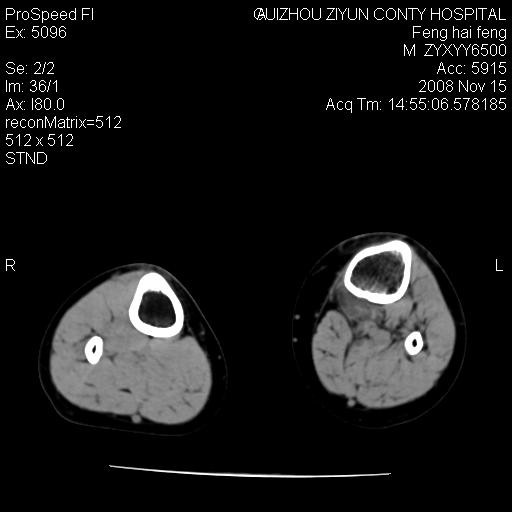

标题: CT16656:M 14Y 左膝关节肿胀一年余。其余病史不详。 [打印本页]

标题: CT16656:M 14Y 左膝关节肿胀一年余。其余病史不详。

考虑左侧髌骨结核;左膝关节滑膜肿胀、增厚,关节囊积液。

左膝滑膜型关节结核可能性大!支持!滑膜型关节结核主要ct表现:关节囊肿胀,积液,关节面见小破坏灶,并见点状死骨!

好大的左腿!考虑左侧髌骨结核,左膝关节滑膜肿胀、增厚,关节囊积液。

左侧髌骨结核;左膝关节滑膜肿胀、增厚,关节囊积液